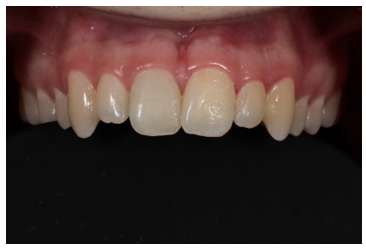

A 22-year-old patient presented to a prosthodontic practice with an complicated fracture of a maxillary central incisor (Fig. 1). The patient was transported to the dental clinic after experiencing trauma to the maxillary anterior teeth during physical fitness training. #8 displayed a mid-crown complete horizontal fracture, the pulpal tissue was exposed, no mobility, and the patient reported a moderate amount of sharp constant pain (Fig. 2). A pulpal and periapical diagnosis of symptomatic irreversible pulpitis and normal apical tissue was made. No other injuries were noted to adjacent teeth or intraoral and extraoral tissue. The fractured segment was brought with the patient and after cleaning with sterile saline it could be easily aligned back on the tooth and the margins displayed a clean fracture (Figs. 3 and 4). The patient was esthetically demanding and required a quick and long-term solution to return back to training as he was a student at Fort Eisenhower. The patient was scheduled for an overseas mission shortly after his school ended.

Figure 1: Initial presentation of patient.